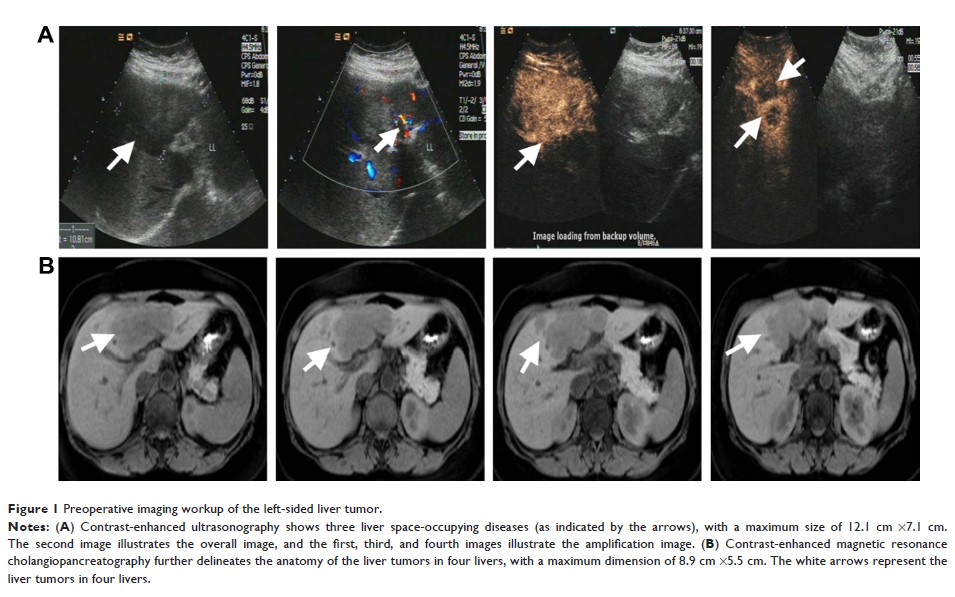

Original Research

- 作者:Ye Yuan, Shi-Lin Li, Yu-Lin Cao, Jun-Jun Li, Qiang-Ping Wang

- 期刊:OncoTargets and Therapy